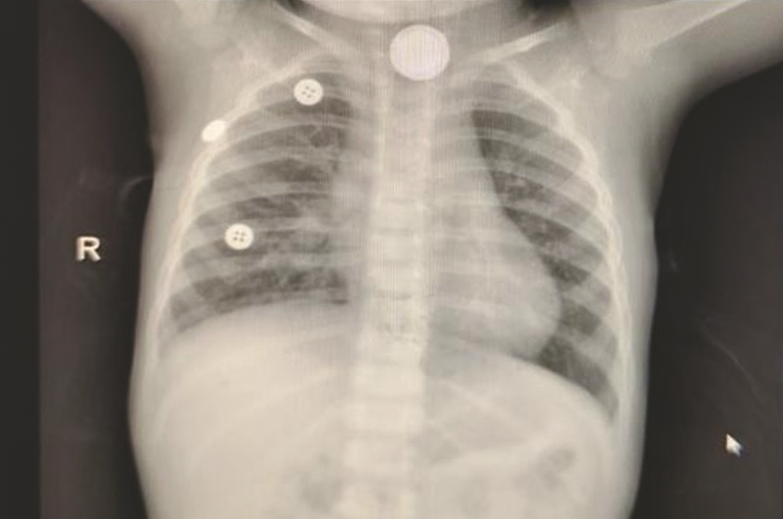

在内镜中心团队人员的精心操作下,细长的内镜轻柔探入,高清画面实时传回:那枚银色的纽扣电池,正紧紧嵌顿在食管入口第一狭窄处!孩子太小,纽扣电池大,电池死死地卡在食管入口处,操作空间有限,电池边缘太滑,种种的困难与挑战摆在医护人员面前,这是一场与时间的拉锯战。过程是艰辛的,但结果是好的,这枚危险的“定时炸弹”终于被完整取出,检查确认食管黏膜仅有轻微损伤,所有人悬着的心终于落地。